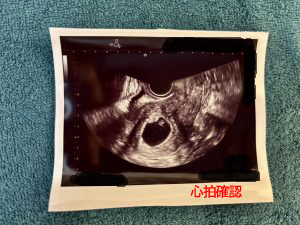

2回目の体外受精で妊娠判定が陽性に!

その後は、つわりを和らげるための鍼灸も行い、順調に妊娠を継続。

約8か月の不妊鍼灸治療を経て心拍確認後、不妊クリニックを卒業されました。